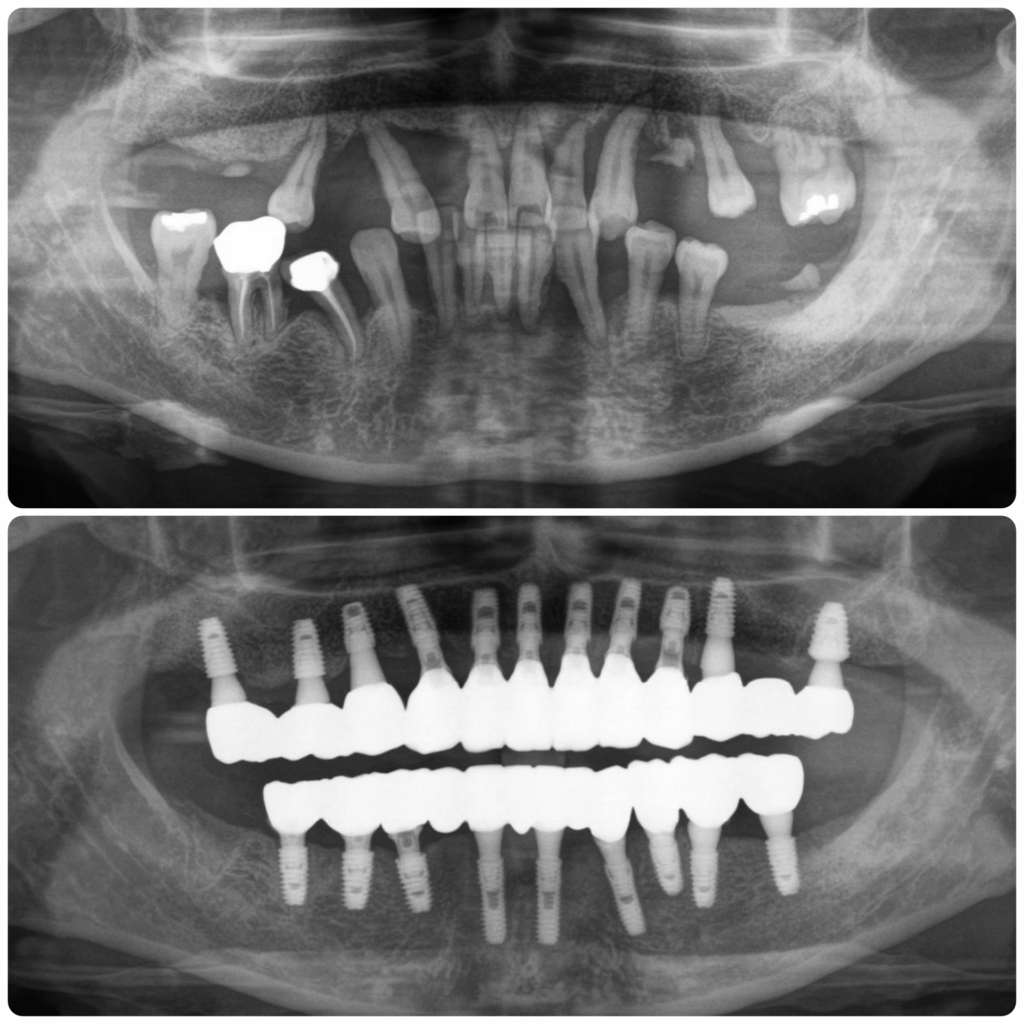

즉시하중 전체임플란트 치료후 파노라마